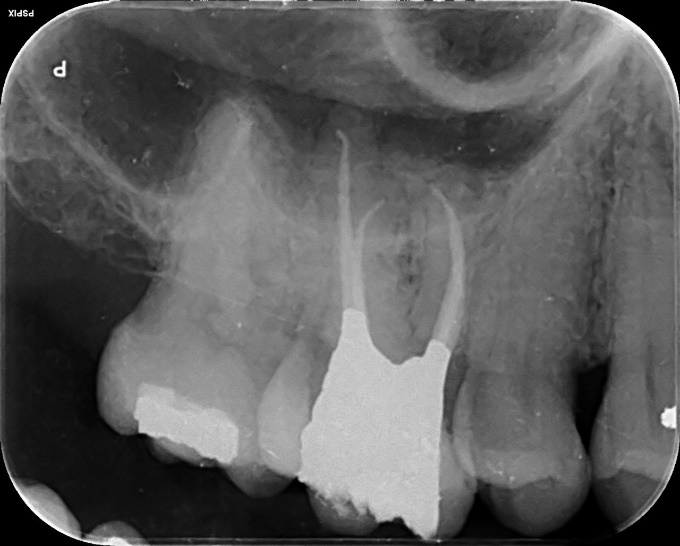

Upper Incisor trauma case primary root canal treatment and rebuild